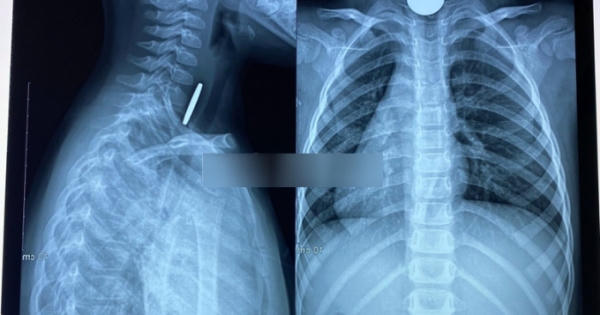

Chiếc đầu kèn đồ chơi làm bằng nhựa không may lọt vào phổi bé trai 6 tuổi, các bác sĩ đã phải rất khó khăn mới gắp được dị vật ra ngoài.